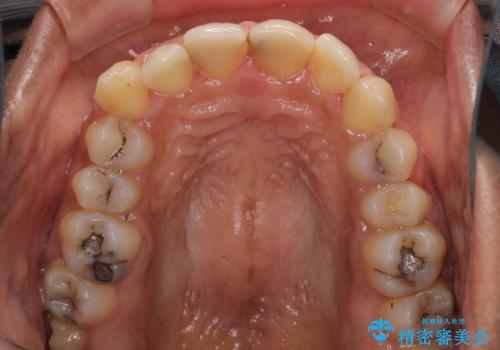

- 上の前歯2本の審美障害を気にして来院された患者様です。樹脂が無造作に充填されており、色合いも形態も不自然で、歯肉も腫れているため、オールセラミッククラウンにて補綴することとしました。

充填されたレジンを取り除いたところ、歯肉の炎症による出血が認められました。セラミッククラウン装着後は歯肉が腫れることもなく、仕上がりも自然な歯のようになり、患者様には大変満足していただきました。